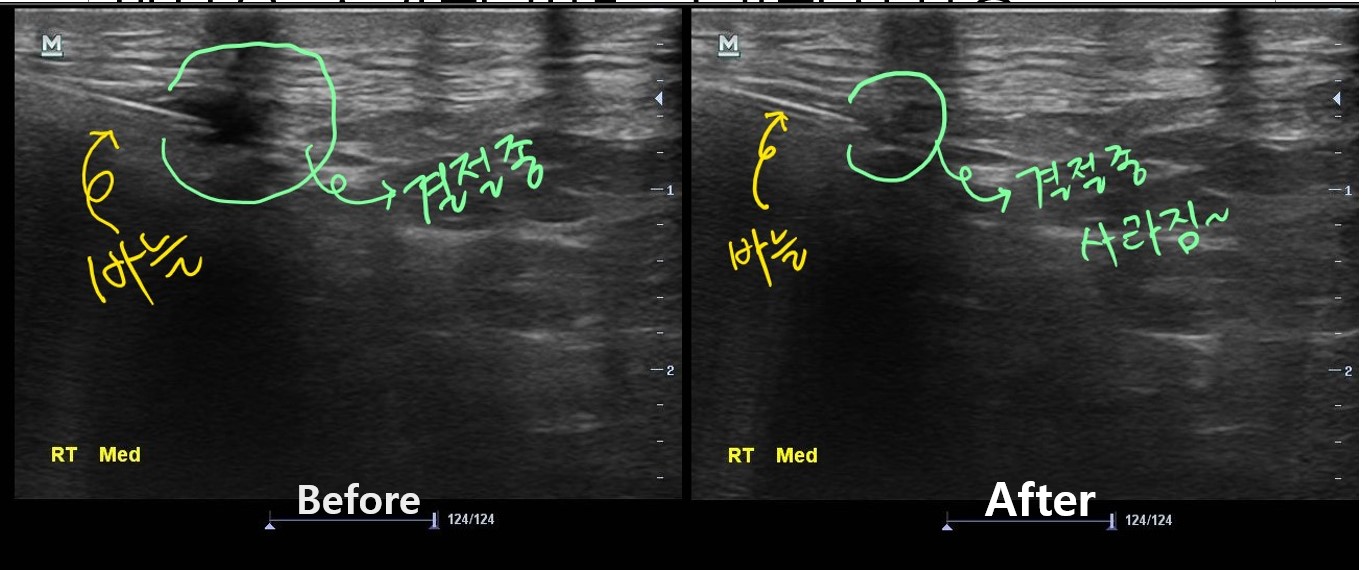

이 환자분의 진짜 문제는 초음파 검사에서 발견되었습니다.

나 : 내측반월판 연골 부위에 물혹이 하나 생겨있습니다.

나 : 네 결절종이라고 하는 건데요... 무릎을 굽히실때 이게 주변 조직을 누르면서 통증이 발생한듯 합니다.

나 : 초음파 보면서 주사기로 물혹속 내용물을 제거해봐야 할거 같습니다.

치료 후 3개월이 지난 현재, 이 환자분은 다행히 물혹이 재발되지 않아 큰 불편함없이 잘 지내고 있습니다. 아직 더 지켜보긴 해야 하지만요...

이런 환자를 만나면 초음파 검사의 필요성과 중요성을 다시 한번 깨닫게 됩니다.